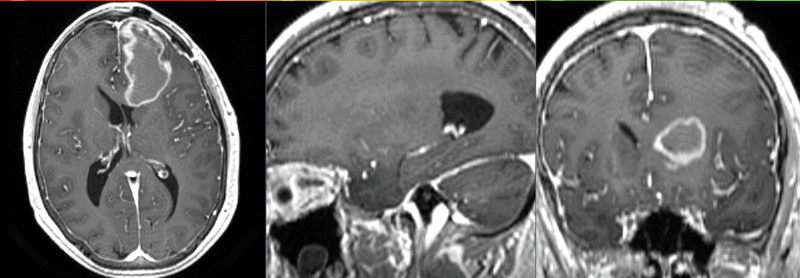

File:RegLib C33 registeredDTI.gif

Size of this preview: 800 × 278 pixels. Other resolutions: 320 × 111 pixels | 928 × 322 pixels.

Original file (928 × 322 pixels, file size: 1.38 MB, MIME type: image/gif)